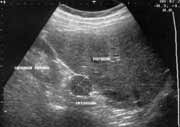

Эхоскопия сегодня - один из наиболее информативных и широкоиспользуемых лучевых методов диагностики. Благодаря простоте выполнения, высокой информативности, безвредности эхоскопия становится методом выбора уже на первом этапе применения инструментальных методов диагностики. Ультразвуковой метод исследования позволил существенно повысить процент ранней и точной диагностики опухолей надпочечников. С внедрением новейших аппаратов стало возможным зарегистрировать в надпочечнике любое объемное образование размером около 1 см. (Рис. 1), что по точности диагностики приближается к компьютерной томографии(1,2.5,6,7).

Рис. 1. Объемное образование до 1 см в диаметре в правом надпочечнике.